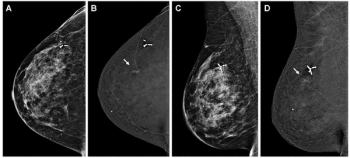

A symptomatic first breast cancer diagnosis, prevailing breast density at a second breast cancer diagnosis and trabecular thickening on surveillance mammography were linked to mammogram-occult ipsilateral breast cancer, according to new research.